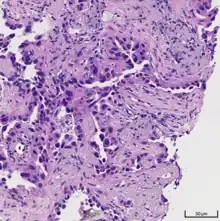

Classification

.jpg.webp)

The majority of lung cancers can be characterized as either small cell lung cancer (SCLC) or non-small cell lung cancer (NSCLC). Lung adenocarcinoma is one of the three major subtypes of NSCLC, which also include squamous carcinoma and large cell carcinoma.[15]

Historically, there has been much debate in the most accurate method of describing adenocarcinoma of the lung and several revisions of classification systems have been published. Most recently, the International Multidisciplinary Classification of Lung Adenocarcinoma was published in 2011 and represents the consensus of several organizations to more accurately describe this specific type of lung cancer.[2] The current classification system aims to more reliably predict prognosis and determination of therapeutic management.[4]

The tumor size, pattern of cell growth, and depth of cell invasion into normal lung tissue are considered in determining classification. The following names represent a step-wise pathologic progression in the natural course of adenocarcinoma development; Adenocarcinoma in situ (AIS), Minimally invasive adenocarcinoma (MIA), and Invasive adenocarcinoma.[15] Invasive adenocarcinoma of the lung includes a heterogenous mixture of subtypes and variants.

The 2011 consensus describes five subtypes of invasive adenocarcinomas based on the cell pattern that is most predominant. These subtypes are described below:

Cell patterns identifying subtypes are associated with prognosis, ranging from favorable (lepidic) to intermediate (acinar and papillary) to poor (micropapillary and solid).[2]